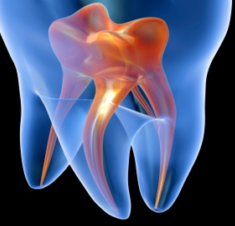

Inlays & Onlays